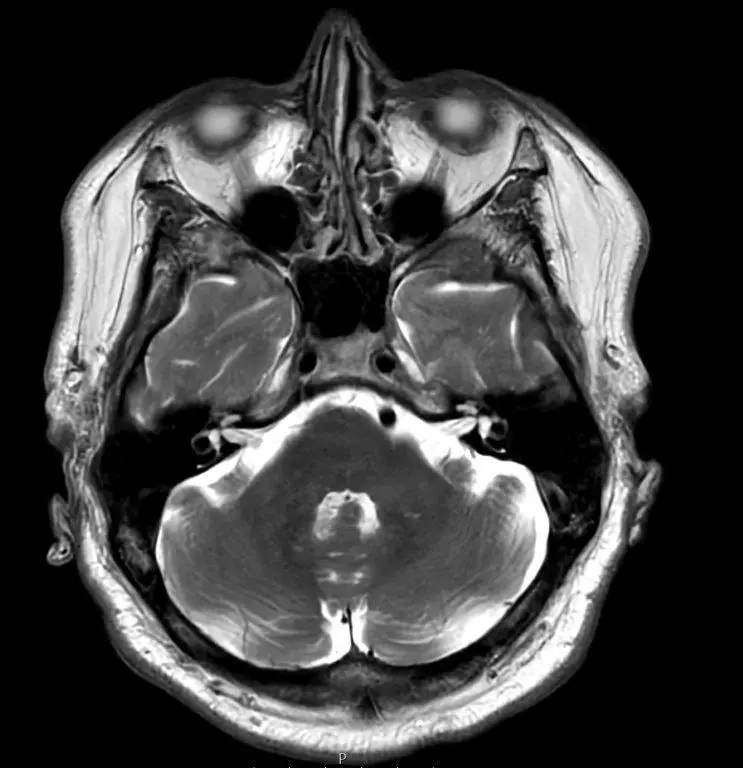

Hvad er en MR-scanning af hjernen?

En MR-scanning af hjernen er en avanceret billedteknik, der bruger magnetfelter og radiobølger til at skabe detaljerede billeder af hjernens strukturer. Metoden har været brugt siden 1980’erne og er i dag det foretrukne værktøj til at opdage forandringer og forhindre alvorlige konsekvenser.

Ved en MR-scanning tages omkring 2.000 detaljerede billeder, som giver et præcist indblik i hjernens anatomi, herunder:

- Hjernestammen og cerebrospinalvæsken, der omgiver hjernen og rygmarven

- Hjernebarken (den grå substans), som styrer kroppens funktioner

- Den hvide substans med nervebaner, der forbinder hjernens forskellige dele

Eksempler på MR-scanninger